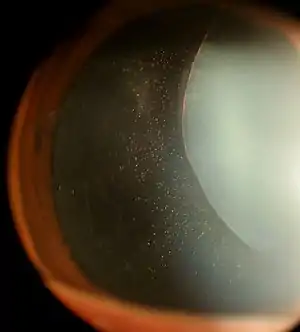

| Ectopia lentis in Marfan syndrome: Zonular fibers are seen. | |

In Marfan syndrome, the health of the eye can be affected in many ways, but the principal change is partial lens dislocation, where the lens is shifted out of its normal position.[15] This occurs because of weakness in the ciliary zonules, the connective tissue strands which suspend the lens within the eye. The mutations responsible for Marfan syndrome weaken the zonules and cause them to stretch. The inferior zonules are most frequently stretched resulting in the lens shifting upwards and outwards, but it can shift in other directions as well. Nearsightedness (myopia), and blurred vision are common due to connective tissue defects in the eye.[16] Farsightedness can also result particularly if the lens is highly subluxated. Subluxation (partial dislocation) of the lens can be detected clinically in about 60% of people with Marfan syndrome by the use of a slit-lamp biomicroscope.[16] If the lens subluxation is subtle, then imaging with high-resolution ultrasound biomicroscopy might be used.[17]